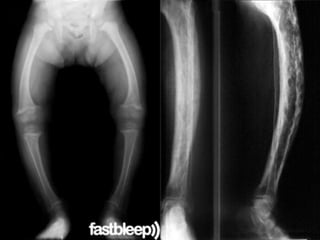

Bone lesions

• During first six months – osteochondritis of long bones

(upp. end of tibia, distal end of radius & ulna)

• Child presents with severe pain, tenderness while

handling with consequent loss of movements  syphilitic

pseudo paralysis.

• Wimberger’s sign- loss of density on the medial side of

upper end of tibia .

• Gummas may involve long & flat bones

• Manifest as diffuse / localized gummatous

osteoperiostitis

• Bones- thickened , tender

• Tibia is most frequently involved, thickening of middle

third causes anterior bowing ‘Sabre tibia’